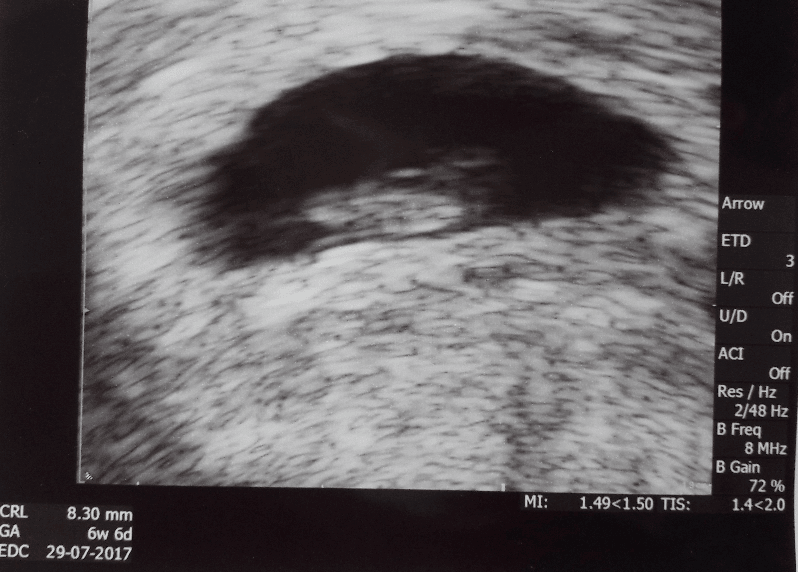

Piekny widok. Teraz z miesiaca na miesiac kropeczka bedzie coraz wieksza na nastepnej wizycie zobaczysz juz wiecej niz tylko kropeczke z bijacym serduszkiemDziewczyny, ja już po wizycie. Nasza Kropeczka już jest większą Kropeczką i ma 8,3 mm.

Słyszeliśmy też przez chwilę bijące serduszkoDostałam rozpiskę leków do końca i mam w ciągu dwóch tygodni stawić się u lekarza, który będzie prowadził ciążę.

Dziewczyny, ja już po wizycie. Nasza Kropeczka już jest większą Kropeczką i ma 8,3 mm.